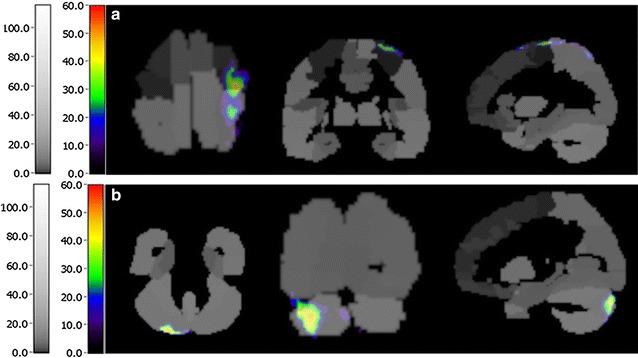

Five participants without forearms (three male, two female, mean age 51 ± 12.89 years, two missing the right side, and three missing the left side) were included in our study. In the clinical assessment, all of the participants received higher scores after training. The results of the SPM analysis indicated that CBF in the precentral gyrus, postcentral gyrus, frontal lobe, temporal lobe and cerebellum was significantly different among the five participants (P < 0.05). Moreover, SPECT-CA showed that the activated brain areas mainly included the precentral gyrus, postcentral gyrus, cerebellum and extensive cerebral cortex.

我们的研究纳入了5名无前臂的参与者(3名男性,2名女性,平均年龄51±12.89岁,2名右侧缺失,3名左侧缺失)。在临床评估中,所有参与者在训练后得分更高。SPM分析结果表明,5名参与者中央前回、中央后回、额叶、颞叶和小脑的脑血流灌注存在显著差异(P<0.05)。此外,SPECT-CA显示激活的脑区主要包括中央前回、中央后回、小脑和广泛的大脑皮层。